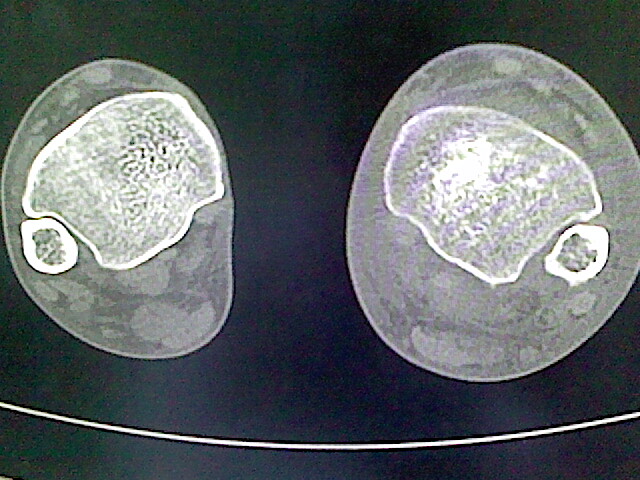

男,76岁,左小腿疼痛,不能站立

本例骨质改变主要表现为滑膜或韧带区的骨侵蚀融解(胫腓联合区骨质破坏无硬化边),距骨后部骨质破坏区有硬化边及死骨样改变.所以,本例考虑关节结核可能性大,绒毛膜结节性滑膜炎多发于中年,且极少见于膝髋以外的关节,骨质硬坏也以压陷吸收为主,有明显的硬化边,骨膜增生呈结节状(可以mr鉴别),所以本例暂除外.

另不除外可引起相似表现的其他炎症如布氏杆菌性关节炎等